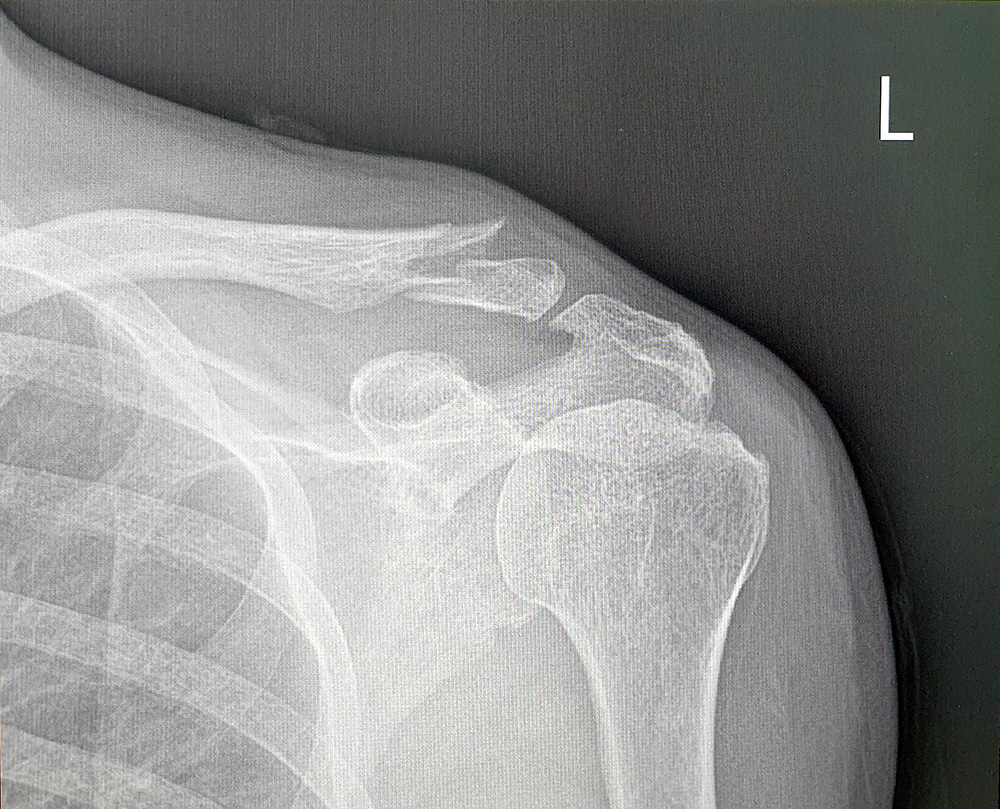

수술전 쇄골골절사진 12월 8일 전신마취를 하고 수술을 하였다. 전신마취의 부작용으로 소변이 안 나와 당직의사를 불러 소변줄을 꼽고, 돌처럼 딱딱해진 변 때문에 항문이 찢어져 며칠간 변을 볼때마다 눈물을 흘렸다. 커다란 멜빵과 보호대를 차고 잠을 자는데, 진통제, 소염제 등 약 때문인지 깊이 잠을 자다가 깨어 나를 얽어 매고 있는 보호대를 수차례 뜯곤 하였다. 진통 소염제 탓인지 시도때도 없이 잠만 자다가 이젠 수술한지 한달이 되어 보호대와 멜빵도 떼고 도수 치료를 기다리고 있다.